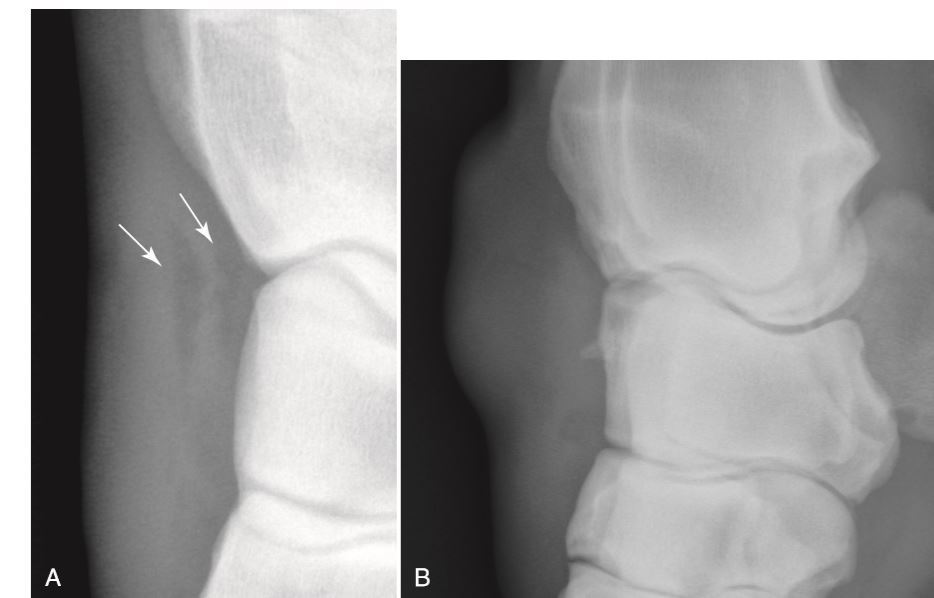

Fusion of the distal radius and ulnar epiphysis should accord when?

3-6 months

The arrow is pointing to the ulnar epiphysis which is normally no fused in this horse at this age…there is incomplete ossification of the carpal bones in this horse.